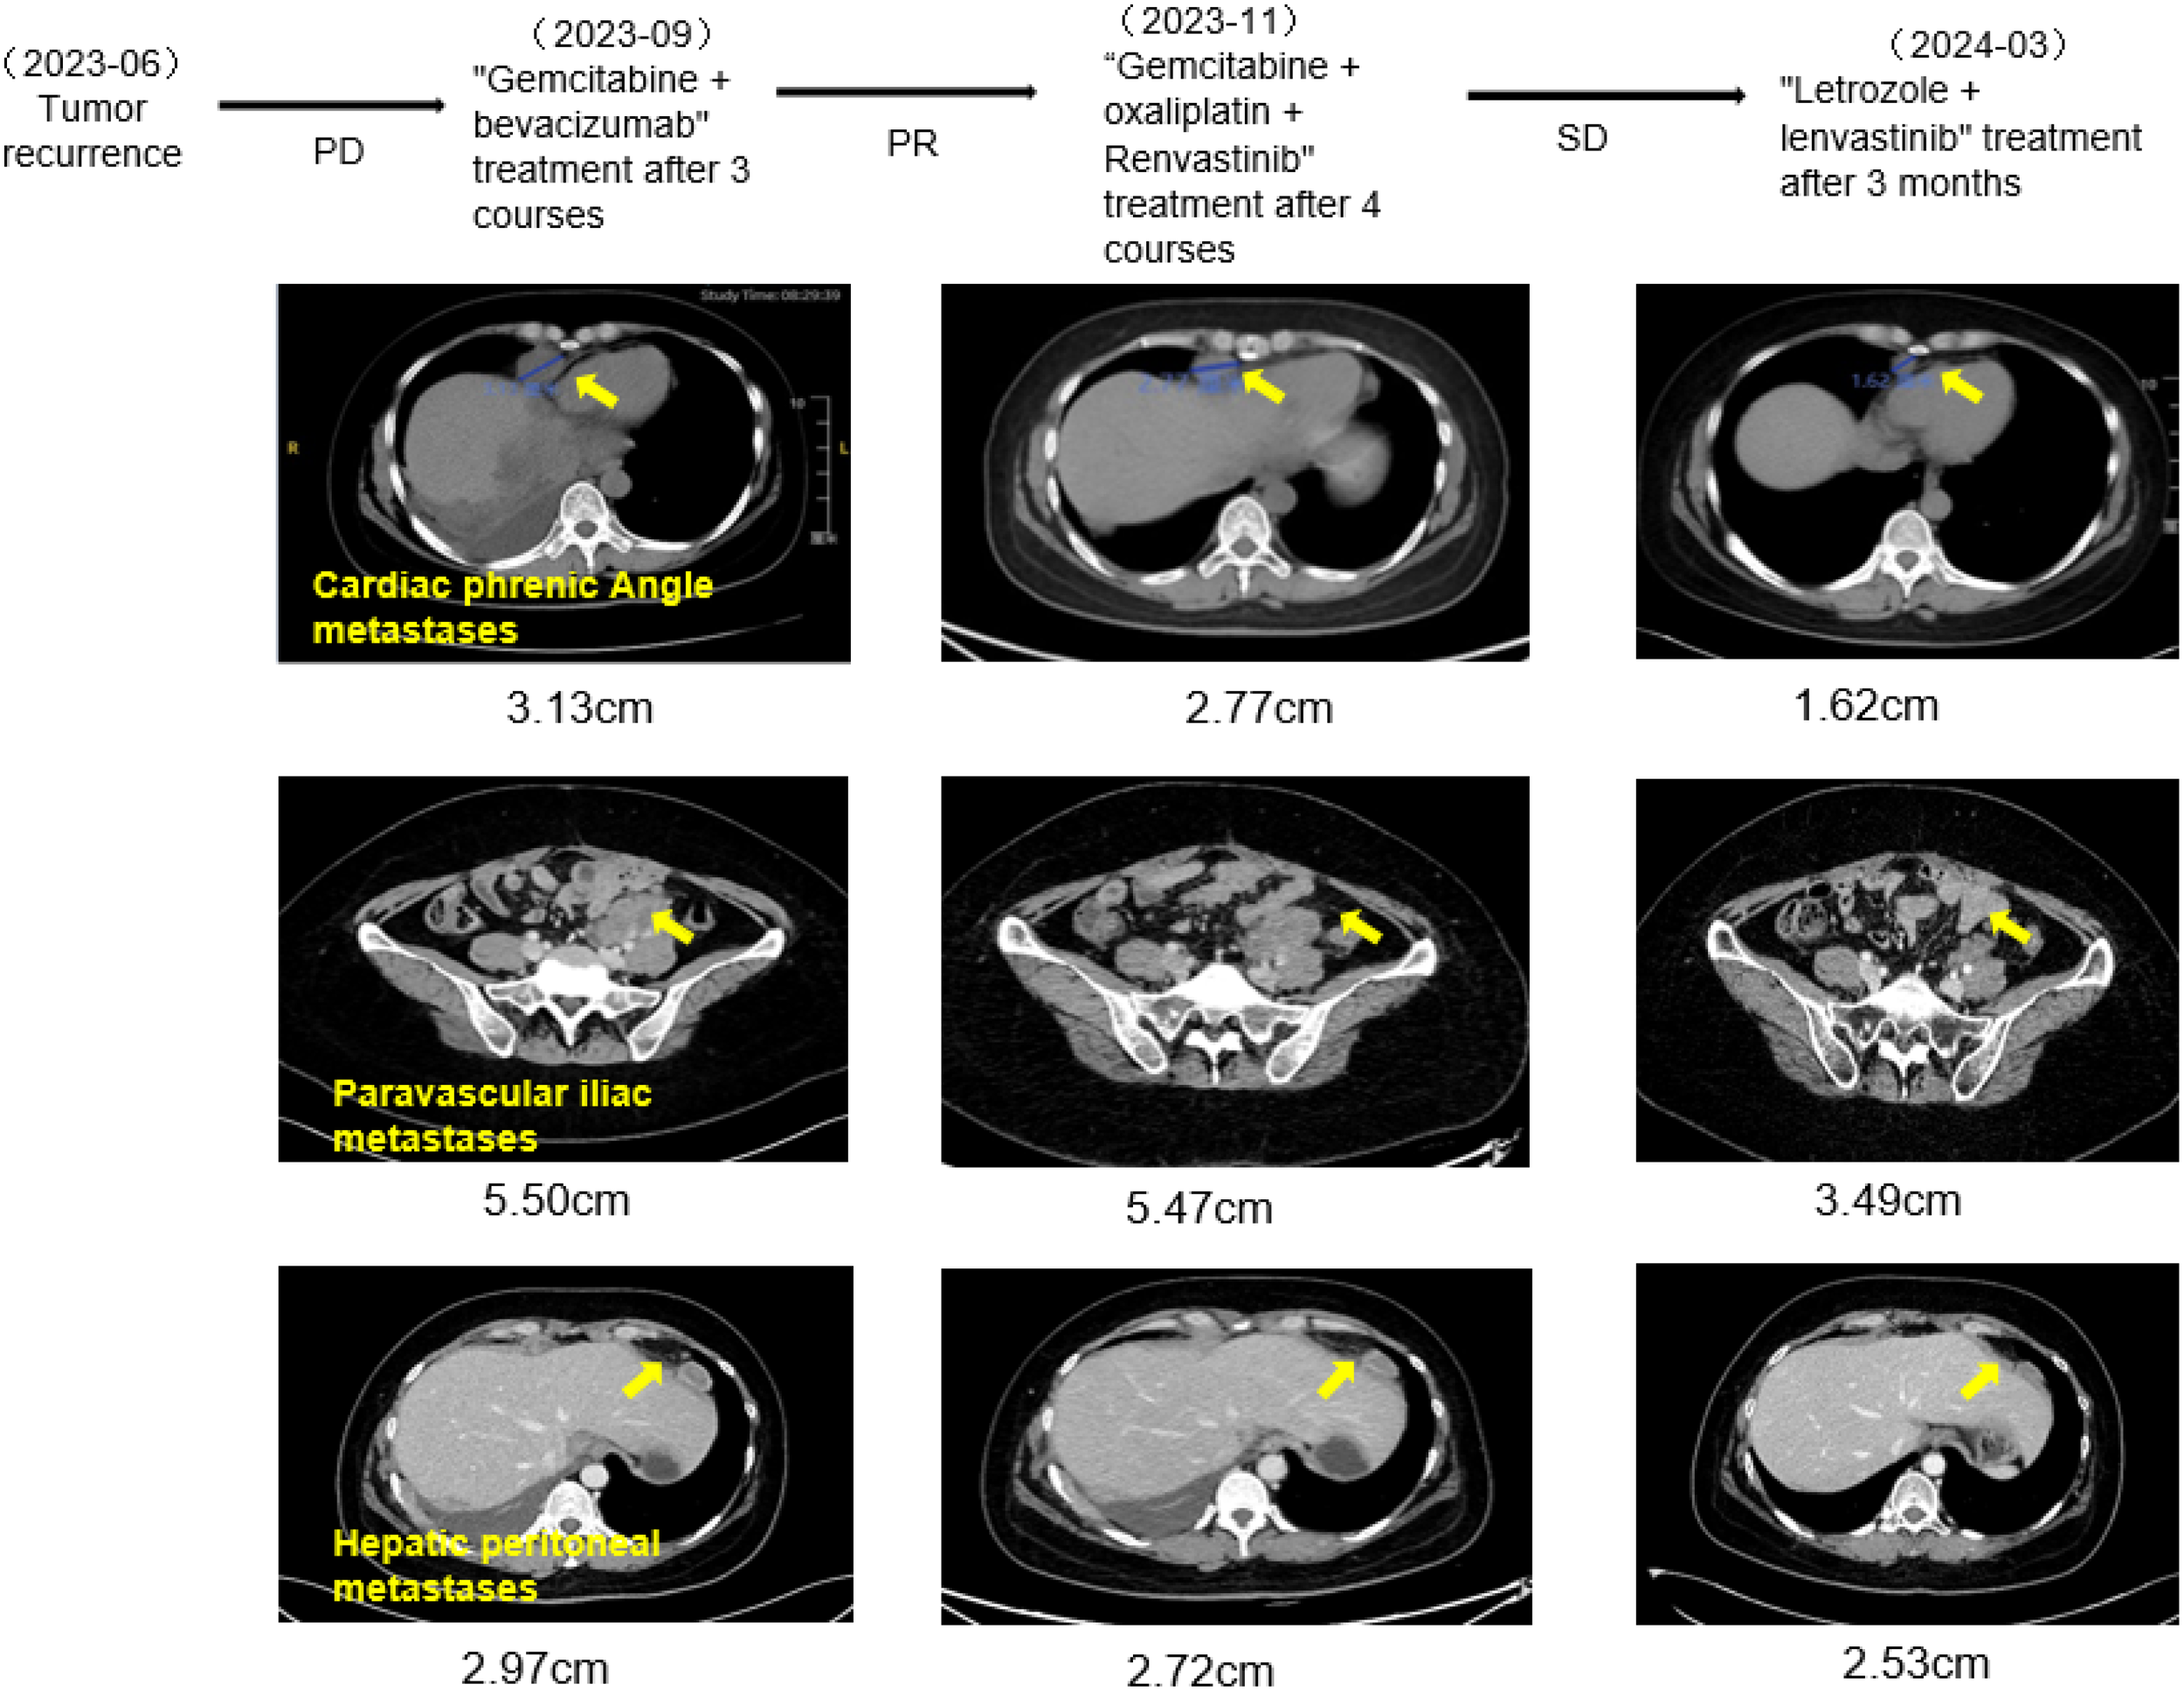

In June 2023, the patient was admitted to the emergency room with chest pain, and a chest CT scan revealed pleural effusion, pleural metastasis, and peritoneal metastasis. Furthermore, the original metastatic foci in the pelvic and abdominal cavities had increased in size compared to previous assessments, indicating further tumor progression. After discontinuing anastrozole endocrine treatment, the patient underwent chemotherapy again in June 2023, given the use of platinum-containing drugs within the last 3 months, the patient was given 3 courses of treatment of gemcitabine on days 1 and 8 in combination with bevacizumab. However, subsequent evaluations indicated continued progression of the metastatic lesions (PD). On September 4, 2023, the treatment of “gemcitabine d1, d8 + oxaliplatin” was replaced, alongside oral lenvatinib at 8 mg once daily. After completing 4 cycles of this treatment, a CT scan indicated a partial reduction in metastatic lesions compared to previous assessments, and the tumor markers gradually declined, indicating a PR status to the treatment. However, the patient discontinued chemotherapy due to the side effects associated with the treatment. Considering the poor response to anastrozole, the patient’s treatment was adjusted on November 20, 2023, to oral maintenance therapy of lenvatinib 12 mg qd combined with letrozole 2.5 mg qd, and the patient has been treated with this regimen for 7 months, with the metastatic lesions progressively reduced, and the tumor markers, such as CA125, have continued to decrease to normal levels, with remarkable therapeutic effects as shown in Figure 4. The patient has now survived for 36 months since the onset of the disease and remains in continuous remission. He is advised to have regular reviews and follow-ups.

Figure 4

CT examination of the patient (the trend of lesion change with the change of treatment regimen).